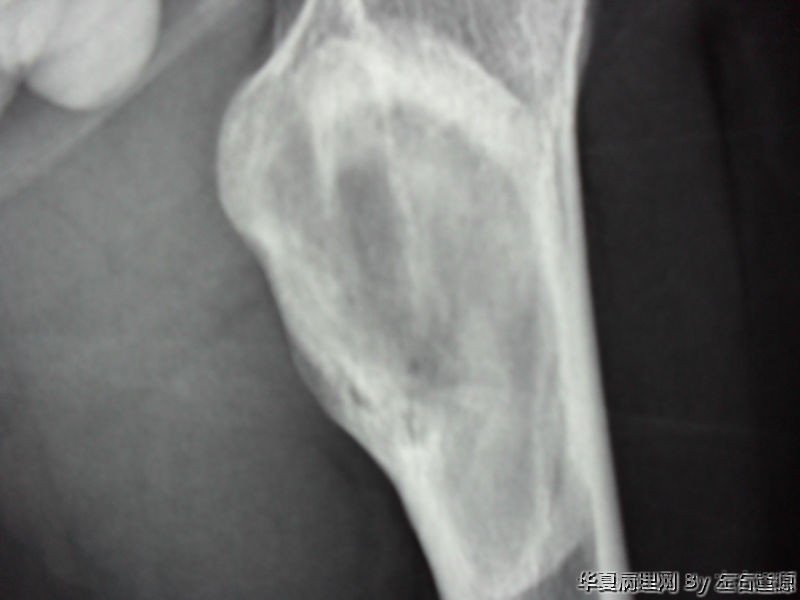

男19岁 左股骨上段异常增殖

• 男19岁 左股骨上段异常增殖图2

图2